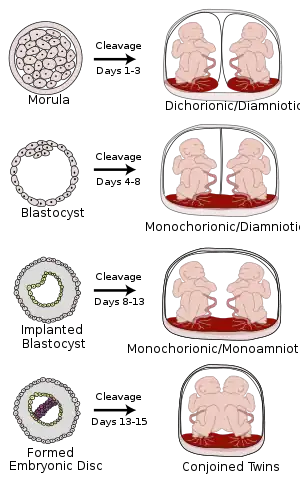

Monochorionic twins are monozygotic (identical) twins that share the same placenta. If the placenta is shared by more than two twins (see multiple birth), these are monochorionic multiples. Monochorionic twins occur in 0.3% of all pregnancies.[1] Seventy-five percent of monozygotic twin pregnancies are monochorionic; the remaining 25% are dichorionic diamniotic.[2] If the placenta divides, this takes place before the third day after fertilization.[2]

Monochorionic twins generally have two amniotic sacs (called Monochorionic-Diamniotic "MoDi"), but sometimes, in the case of monoamniotic twins (Monochorionic-Monoamniotic "MoMo"), they also share the same amniotic sac. Monoamniotic twins occur when the split takes place after the ninth day after fertilization.[2] Monoamniotic twins are always monozygotic (identical twins).[3] Monochorionic-Diamniotic twins are always monozygotic.